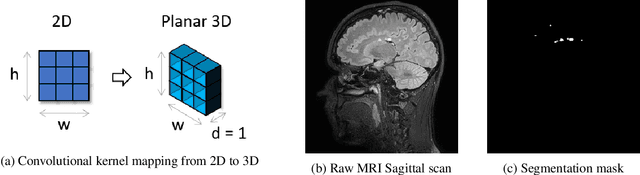

Abstract:We present a novel approach of 2D to 3D transfer learning based on mapping pre-trained 2D convolutional neural network weights into planar 3D kernels. The method is validated by the proposed planar 3D res-u-net network with encoder transferred from the 2D VGG-16, which is applied for a single-stage unbalanced 3D image data segmentation. In particular, we evaluate the method on the MICCAI 2016 MS lesion segmentation challenge dataset utilizing solely fluid-attenuated inversion recovery (FLAIR) sequence without brain extraction for training and inference to simulate real medical praxis. The planar 3D res-u-net network performed the best both in sensitivity and Dice score amongst end to end methods processing raw MRI scans and achieved comparable Dice score to a state-of-the-art unimodal not end to end approach. Complete source code was released under the open-source license, and this paper complies with the Machine learning reproducibility checklist. By implementing practical transfer learning for 3D data representation, we could segment heavily unbalanced data without selective sampling and achieved more reliable results using less training data in a single modality. From a medical perspective, the unimodal approach gives an advantage in real praxis as it does not require co-registration nor additional scanning time during an examination. Although modern medical imaging methods capture high-resolution 3D anatomy scans suitable for computer-aided detection system processing, deployment of automatic systems for interpretation of radiology imaging is still rather theoretical in many medical areas. Our work aims to bridge the gap by offering a solution for partial research questions.